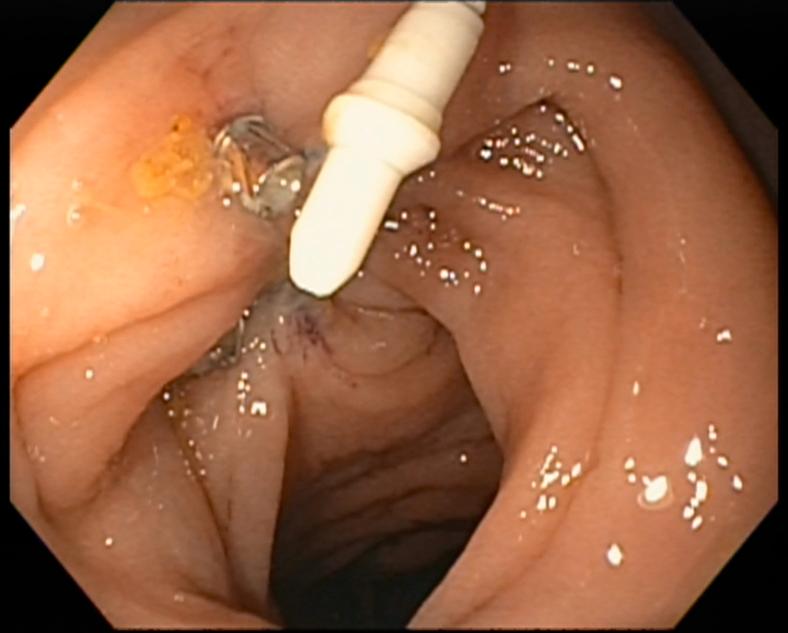

Video 1Use of a novel endoscopic tack and suture system for the management of pancreatocolonic fistula.

视频1:使用新型内镜钉合与缝合系统治疗胰结肠瘘